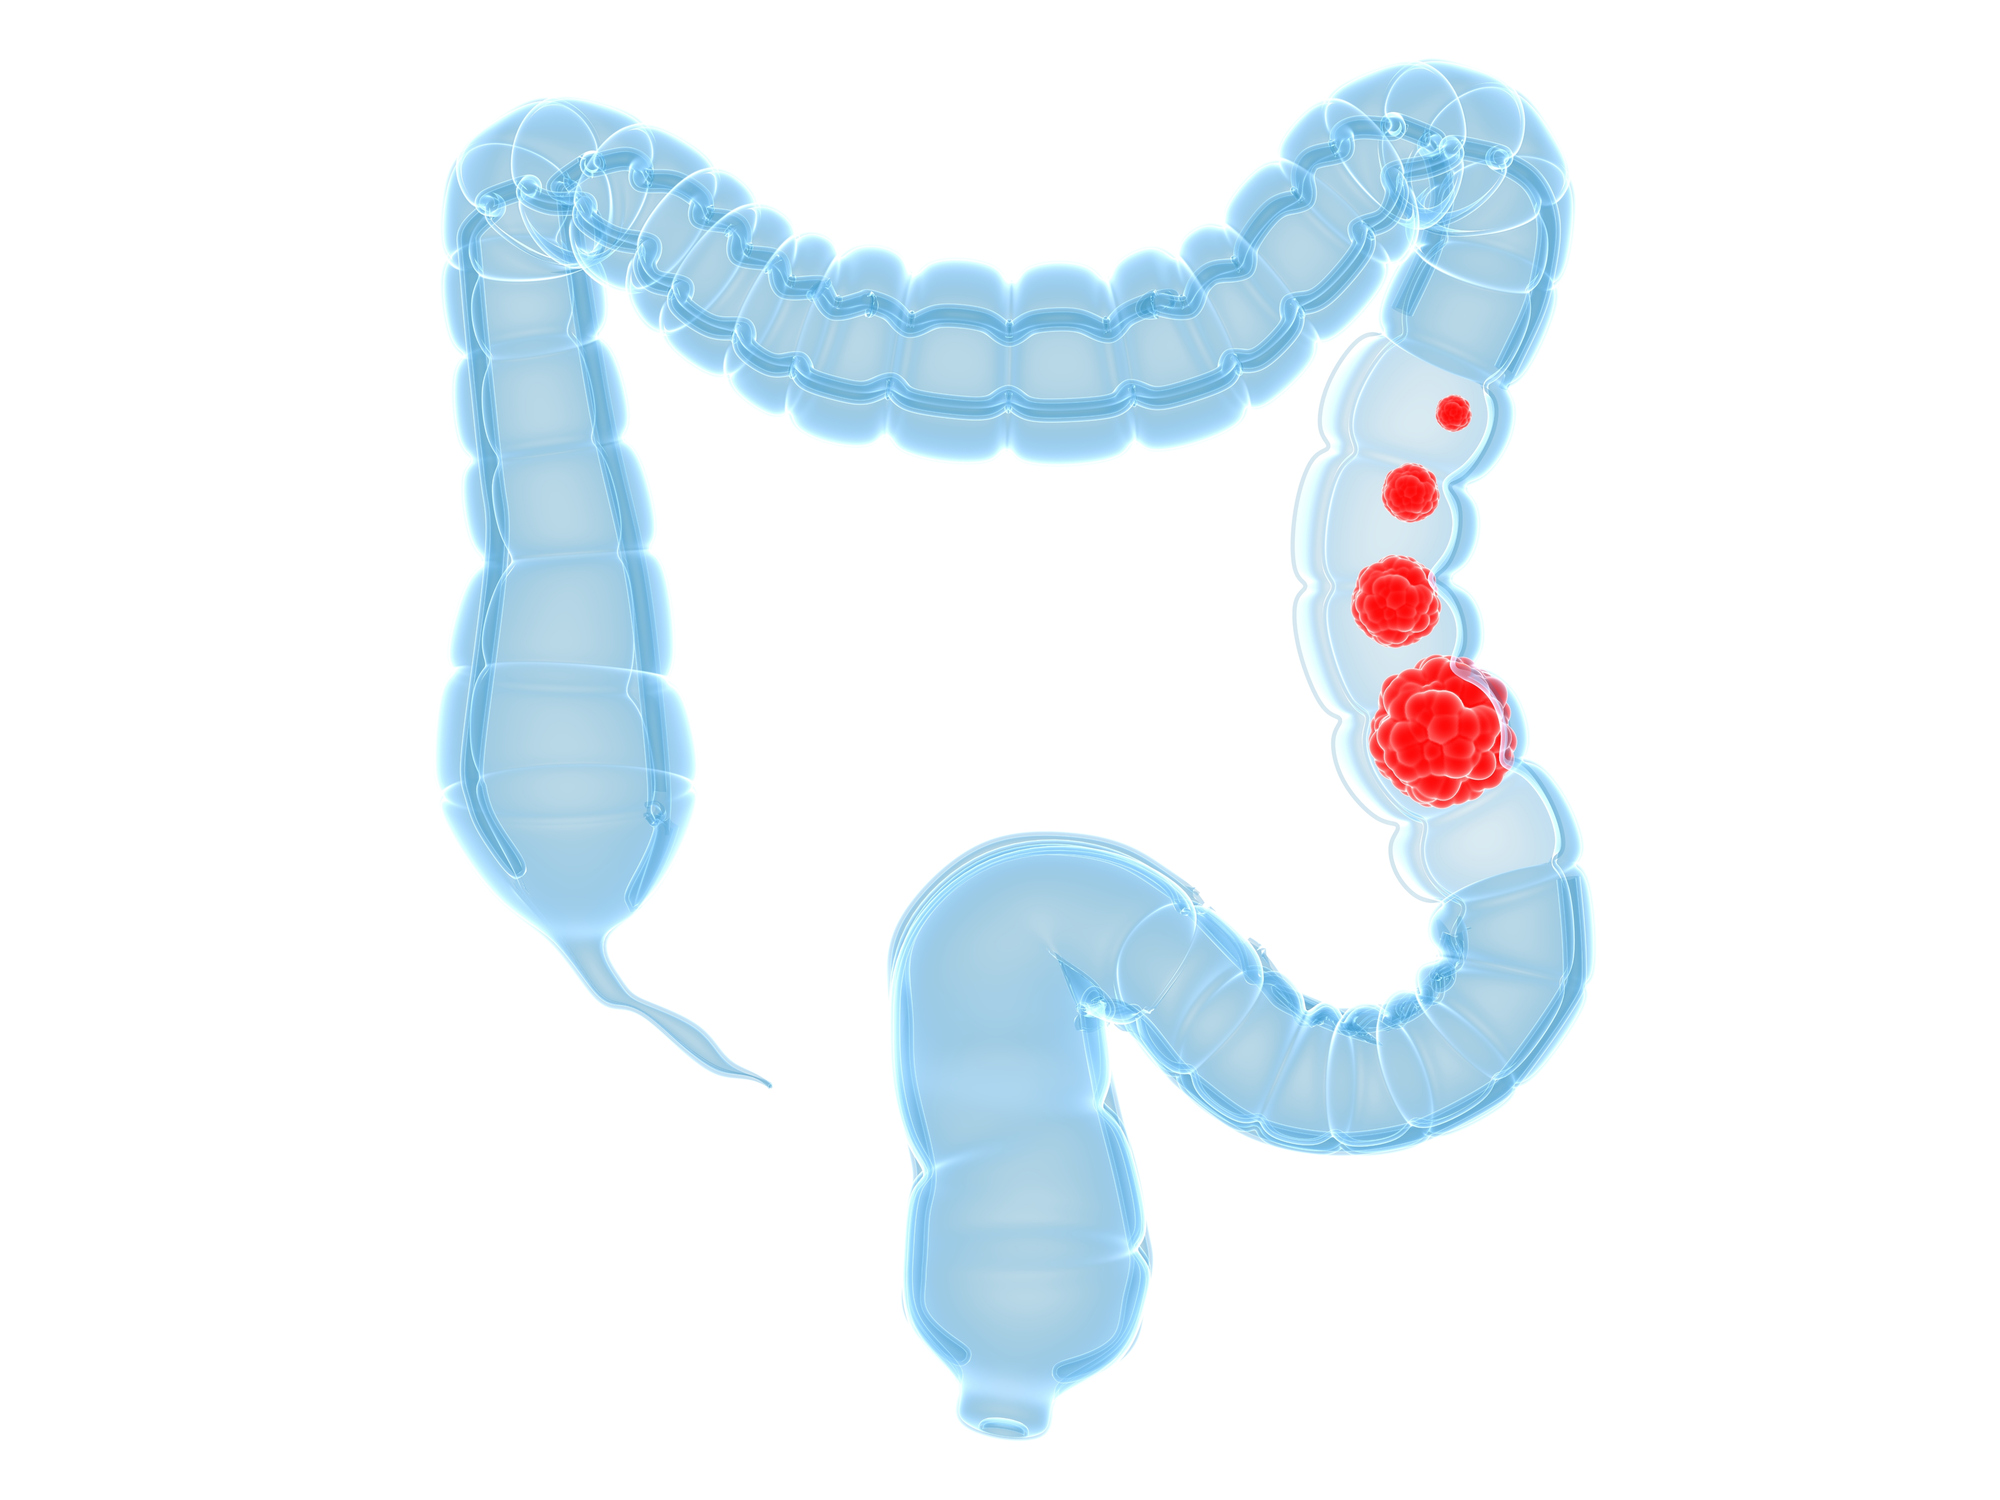

This week’s health news roundup includes recent stories about celiac disease, ulcerative colitis, rheumatoid arthritis, fibromyalgia, and inflammatory bowel disease (IBD). This week, we discussed the benefits of going gluten-free in celiac disease, possible treatment for ulcerative colitis, risk of cancer in rheumatoid arthritis, positive impact of aquatic aerobics on fibromyalgia patients, and the problem ...click here to read more